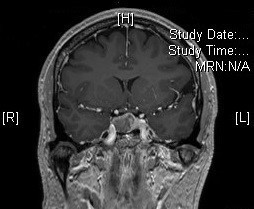

Devant l’anomalie du champ visuel, l’examen suivant est réalisé

Coupe coronale

L’examen montre une lésion au niveau hypophysaire typique d’adénome

L’IRM est l’examen de référence pour les adénomes hypophysaires. On définit un macro-adénome par sa taille supérieure à 10 mm de diamètre.